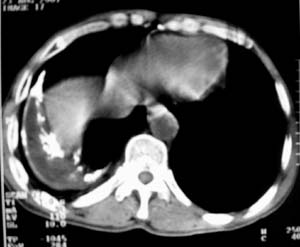

男,54岁,无任何不是感.体检发现右肺部阴影.现行ct进一步确诊.

右侧胸廓塌陷,肋间隙变窄,肋骨增生变粗,脏壁层胸膜肥厚、钙化。符合陈旧性结核性脓胸改变

右侧包裹性积液伴胸膜钙化.

右侧包裹性积液并胸膜钙化,性质还是结合穿刺细胞学检查的好,结核性、化脓性均会有钙化。

右侧胸膜肥厚、粘连、钙化。

周围都钙化了应该不是积液了吧,这样都没有不适感,病史不详